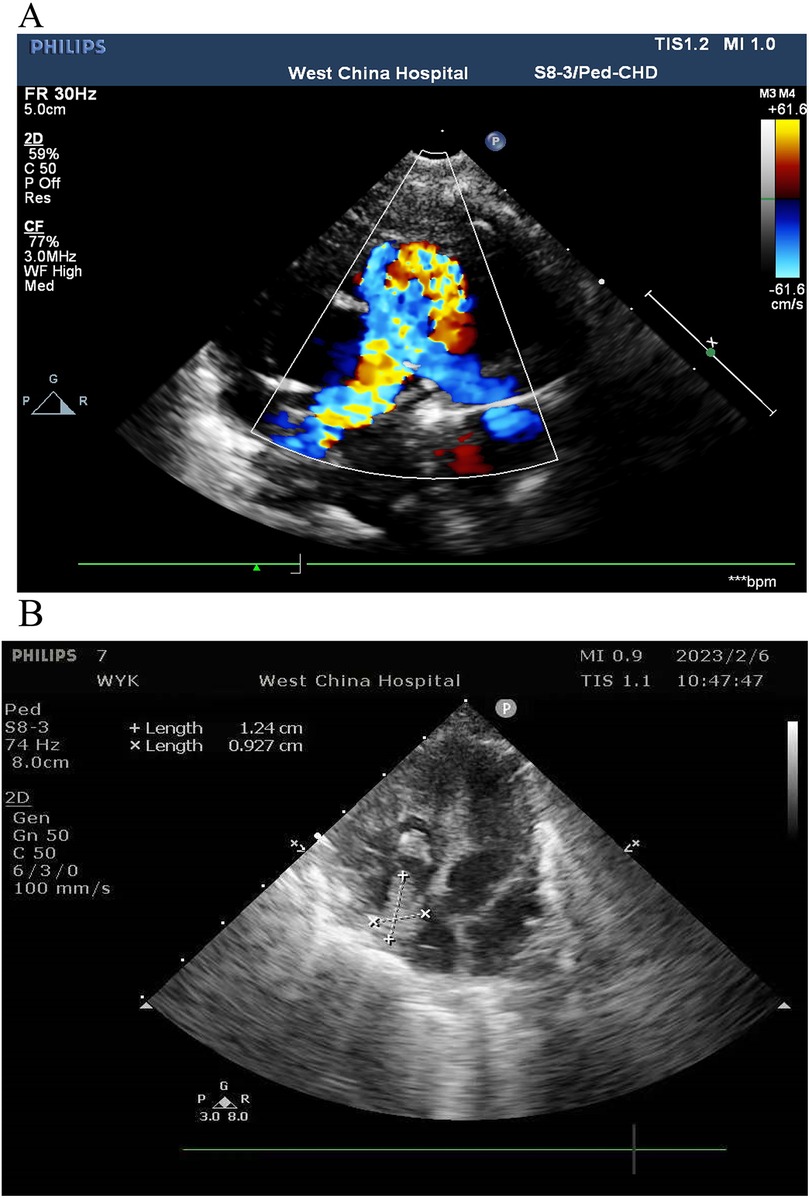

An 11-day-old female neonate was diagnosed with severe pulmonary valve stenosis during the fetal period. She was born at 40 1/7 weeks' gestation with a birth weight of 3,450 g and was admitted to another hospital upon birth for prostaglandin E1 (alprostadil) treatment to maintain patency of the ductus arteriosus (PDA). After 1–2 days, she developed dyspnea, abdominal distension, and oliguria, and was then transferred to a different hospital. The preoperative cardiac ultrasound revealed severe pulmonary valve stenosis (Figure 1A). Subsequently, due to the large PDA, surgical repair of the pulmonary valve stenosis, arterial catheter ligation, and tricuspid valvuloplasty were performed under cardiopulmonary bypass. During the surgery, the partial valve was resected, and the pulmonary artery incision was closed with an autologous pericardial patch to augment the pulmonary artery sinus. Postoperative cardiac ultrasonography revealed an approximately 12 mm × 9 mm right atrial thrombus (Figure 1B), for which low-molecular-weight heparin was administered for anticoagulation. “The preoperative cardiac ultrasound was normal and is shown in Figure 1A”. The cardiac ultrasound shows severe pulmonary valve was stenosis rather than normal. The infant received two central catheters that were placed in the right femoral vein and left femoral artery, respectively. However, 6 days after cardiac surgery, her abdominal symptoms worsened. Abdominal paracentesis revealed ascitic fluid with bile, and an abdominal X-ray suggested a gastrointestinal perforation (Figure 2). An abdominal drainage tube was inserted. After 48 h of worsening symptoms, she was transferred to our hospital.

Ultrasound images from West China Hospital. Image A displays a Doppler ultrasound with blue and red color mapping, indicating blood flow velocity. Image B shows a grayscale ultrasound with measurements of length marked by crosses, displaying dimensions of 1.24 centimeters and 0.927 centimeters. Both images include technical details at the edges.

Figure 1. (A) Preoperative cardiac ultrasound. (B) Postoperative cardiac ultrasound.